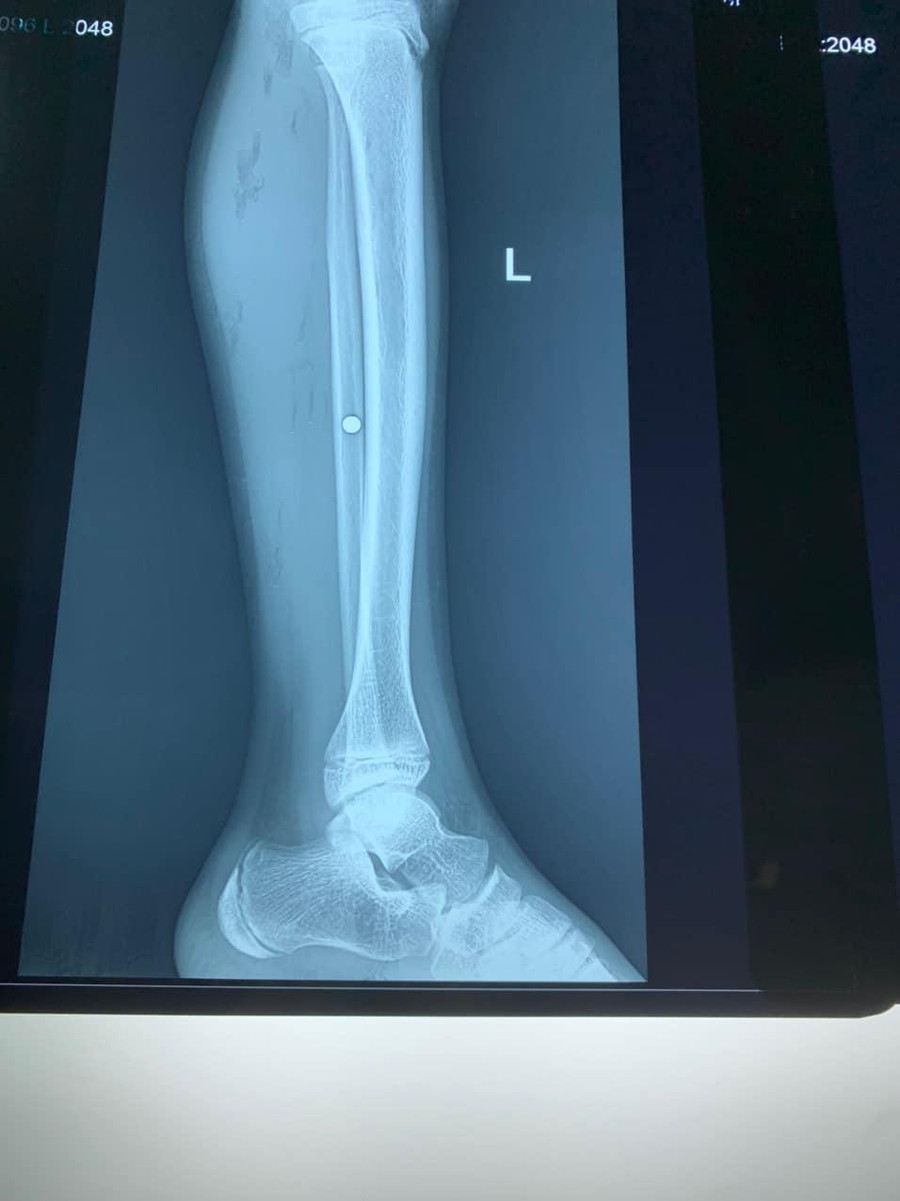

Ngay sau khi tiếp nhận, các bác sĩ thăm khám và làm các chỉ định cận lâm sàng. Kết quả chụp X-quang cho thấy, cẳng chân trái của bệnh nhân bị găm 1 dị vật có kích thước 0,3 cm, cơ cẳng chân trái bị dập nát từ vết thương do hỏa khí gây nên.

|   Phim X-quang cho thấy viên đạn nằm ở cẳng chân bệnh nhi. Ảnh: BV.  |

Sau khi cố định dị vật, các bác sĩ đã tiến hành phẫu thuật lấy được 1 dị vật là mảnh đạn vỡ có đường kính khoảng 1-2mm, đạn dạng bi từ cẳng chân trái của bệnh nhi.